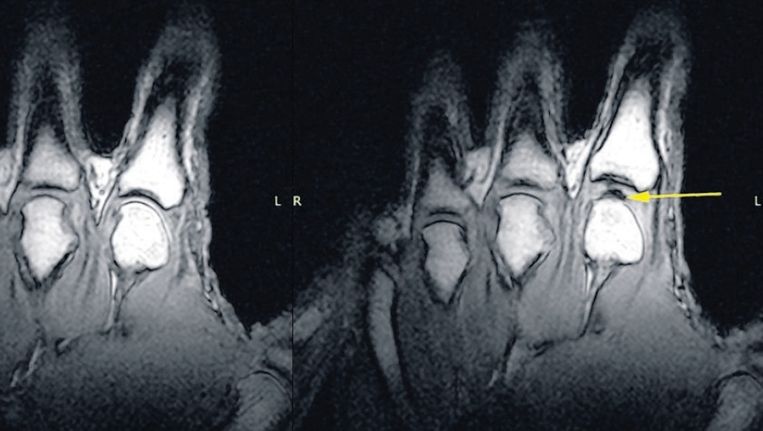

Het knakken van je gewrichten kan verschillende oorzaken hebben. Een veelvoorkomende oorzaak is het vrijkomen van lucht of gassen in het gewricht wanneer je het beweegt. Dit wordt ook wel het “cavitatie” fenomeen genoemd. Bij het bewegen van het gewricht wordt het drukverschil binnen het gewricht gecreëerd, waardoor de opgeloste gassen in het gewrichtsvloeistof vrijkomen en het geluid van het knakken produceren.

Bij artrose kan het voorkomen dat de gewrichten een krakend geluid maken bij bewegen. Het krakende geluid wordt veroorzaakt doordat het kraakbeen en onderliggende bot van structuur veranderen. Het kraken is op zichzelf niet schadelijk of pijnlijk.Gelukkig is het knakken van je vingers helemaal niet slecht voor je, je krijgt er geen ontstekingen of versleten botten van. Maar het kan wel irriteren en zelfs pijn doen als je het heel vaak doet!

Bij artrose kan het voorkomen dat de gewrichten een krakend geluid maken bij het bewegen. Dit krakende geluid wordt veroorzaakt doordat het kraakbeen en het onderliggende bot van structuur veranderen. Hoewel het kraken an sich niet schadelijk of pijnlijk is, kan het wijzen op een onderliggende aandoening zoals artrose. Het kan ook betekenen dat het gewricht niet goed gesmeerd of stabiel is. Daarom is het altijd verstandig om bij aanhoudend kraken en eventuele pijnklachten een arts te raadplegen voor verder onderzoek en advies.